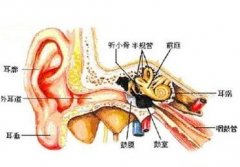

中耳炎有哪些常见的症状

中耳炎,就是我们日常生活中所说的“烂耳朵”,其实是鼓室粘膜的炎症,由细菌入侵了鼓室所致。中耳炎的症状其实非常明显,在生活中很容易看出。... [详情] 文章日期 :16-11-05